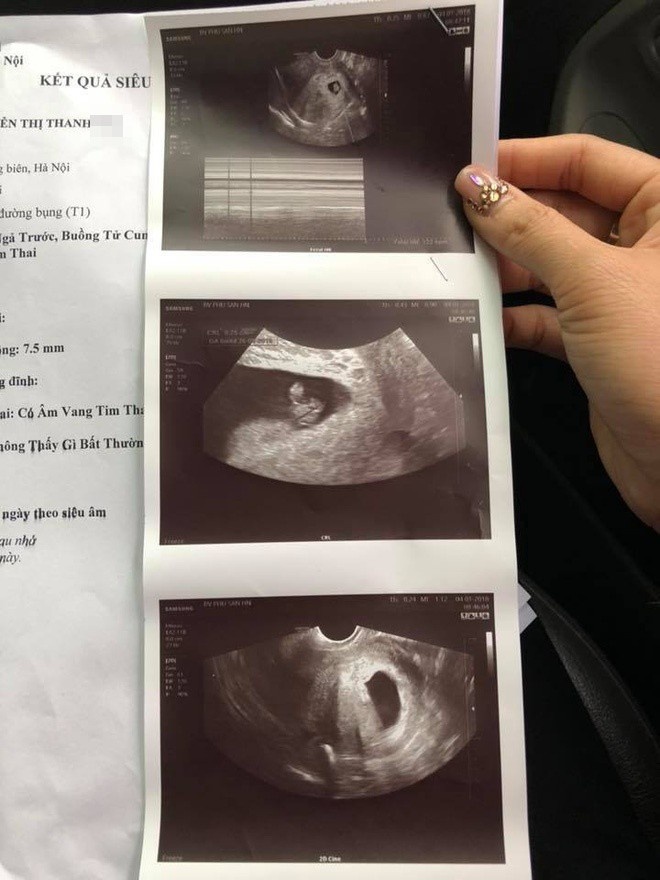

![]() |

| Kết quả siêu âm tại BV Phụ sản Hà Nội cho thấy thai nhi vẫn phát triển bình thường. Ảnh: BNCC. |